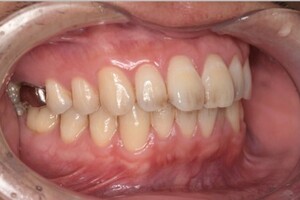

Before

After

基本情報

| 年齢・性別 | 52歳・女性 |

| 主訴 | クリーニングしたい |

| 治療内容 | スケーリング・PMTC |

| 治療期間 | 60分 |

| 治療費 | 約7,000円 |

| リスク・副作用 | 知覚過敏、歯肉退縮 |

| 治療方針 | 歯石とステインを除去して、今後は定期検診でのクリーニングと併せてガムピーリングやホワイトニングを行います。 |

| 担当者所見 | 歯肉の色素沈着が目立つため、ガムピーリングを行いながらホワイトニングを行うことをおすすめします。 |